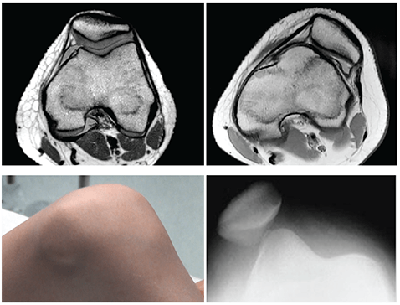

A new algorithm, based on data from 250 children and teens treated for a first-time patellar dislocation could help pediatric specialists predict the likelihood of a recurrent dislocation.

They identified four significant demographic and radiographic risk factors: skeletal immaturity, trochlear dysplasia, a history of contralateral dislocation, and a Caton-Deschamps index (measuring patella height) of greater than 1.45.